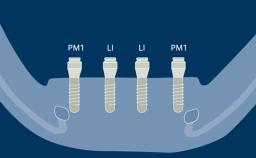

As implant dentistry has evolved, the esthetic outcome of implant therapy has gained increasing importance. As a result both patients and those in the dental profession have become increasingly interested in the attractive esthetic characteristics of all-ceramic prostheses. Extensive research is being devoted to developing, testing, and reviewing the characteristics and performance of ceramic materials in connection with implant therapy. Nevertheless each patient is unique, and it is important to ensure that the appropriate prosthodontic material is selected for each case. This step often requires a team approach in which both the prosthodontic dentist and the dental technician are involved. This module will discuss the different parameters that should influence the decision-making process for selection and use of ceramic materials in implant prostheses.

- describe prosthodontic indications for ceramic materials in implant prostheses and abutments